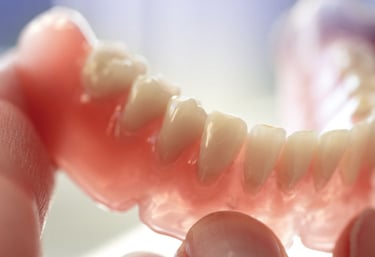

Prosthodontics

Crown and Bridge work (PFM, Zirconia, E max etc.) Temporization Laminates/Veneers Removable Complete Denture Osteoplasty Cast Partial denture Flexible denture